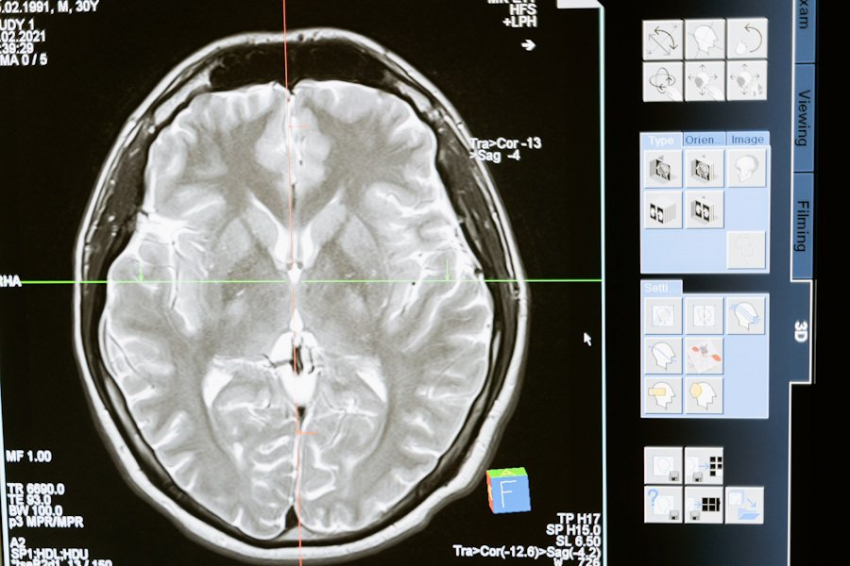

Издание BBC опубликовало статью о том, что происходит в нашем мозге, когда мы чувствуем мотивацию или её отсутствие. Нейропсихологи объясняют, что ключевую роль в этих процессах играют два важных участка мозга — миндалина и префронтальная кора. Миндалина отвечает за наши эмоции, включая страх и тревогу, а префронтальная кора помогает планировать и принимать решения.